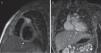

Cardiac CT scan. The proximal giant-sized aneurysmal dilatation in the LAD and RCA can be seen in the three views of the multiplanar reconstruction: axial (image 1), coronal (image 2), and sagittal (image 3); the 3D reconstruction (image 4) accurately shows the location, extension and size of the aneurysms. Localisation of hypoperfusion in the inferior wall, necrosis and lack of viability in one segment (image 1) and hypoperfusion without signs of myocardial injury in the LAD region (image 2).

Asymptomatic intra-aneurysmal thrombosis was detected in one patient (case 3), initially by echocardiography and later by CCTA (Fig. 2) with origin in the right coronary artery (RCA), with a maximum diameter of 13mm, and in the ostial left anterior descending coronary artery (LAD). The patient received systemic thrombolytic therapy with r-TPA, infliximab, abciximab and IV heparin, and had mild systolic dysfunction. Magnetic resonance with IVPD confirmed that the thrombus was old due to the presence of necrosis in the septal and posterior regions and of collateral vessels in some areas. Treatment with ASA, acenocoumarol, angiotensin-converting enzyme inhibitors, carvedilol and spironolactone continued after discharge.

Another patient (case 1) received a diagnosis of intra-aneurysmal thrombosis in the RCA, with prescription of IV heparin sodium and r-TPA, and evidence of mild systolic dysfunction in the left ventricular ejection fraction (LVEF). Follow-up echocardiograms showed that the thrombus had dissolved and the LVEF had normalised, the follow-up CCTA confirmed the absence of intra-aneurysmal thrombotic lesions, and MRI with IVDP ruled out the presence of ischaemic or necrotic lesions and evinced the normalisation of LVEF. The treatment prescribed at discharge was prophylactic antithrombotic therapy and captopril as the sole therapy for myocardial function.

Patients made periodic follow-up visits on an outpatient basis that included electrocardiography, echocardiography every 3–6 months and CCTA every 12 months, and at least one myocardial perfusion scan (earlier cases) or a MRI scan with IVDP (Fig. 3) to assess function for the purposes of prognostication, which was repeated periodically in the 2 patients that had coronary thrombosis. A coronary angiogram was performed in the 3 earliest patients and in the 2 recent patients with intracoronary thrombosis after the initial phase of the disease (Fig. 4). The first 3 patients underwent ergometric stress testing, which they tolerated well, with normal findings in all.